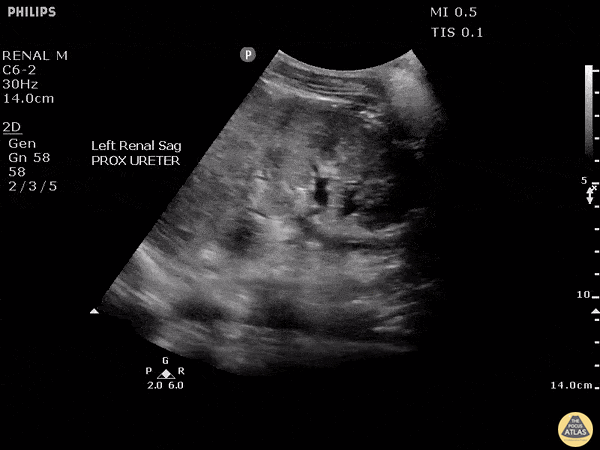

Renal/GU - High Grade Pyelonephritis With Urothelial Thickening

Although most cases of uncomplicated pyelonephritis will appear normal on ultrasound, urothelial thickening might be observed. It should be noted that this can also be observed in different clinical contexts including urolithiasis, stents and malignancy. Image courtesy of Robert Jones DO, FACEP @RJonesSonoEM Director, Emergency Ultrasound; MetroHealth Medical Center; Professor, Case Western Reserve Medical School, Cleveland, OH View his original post here